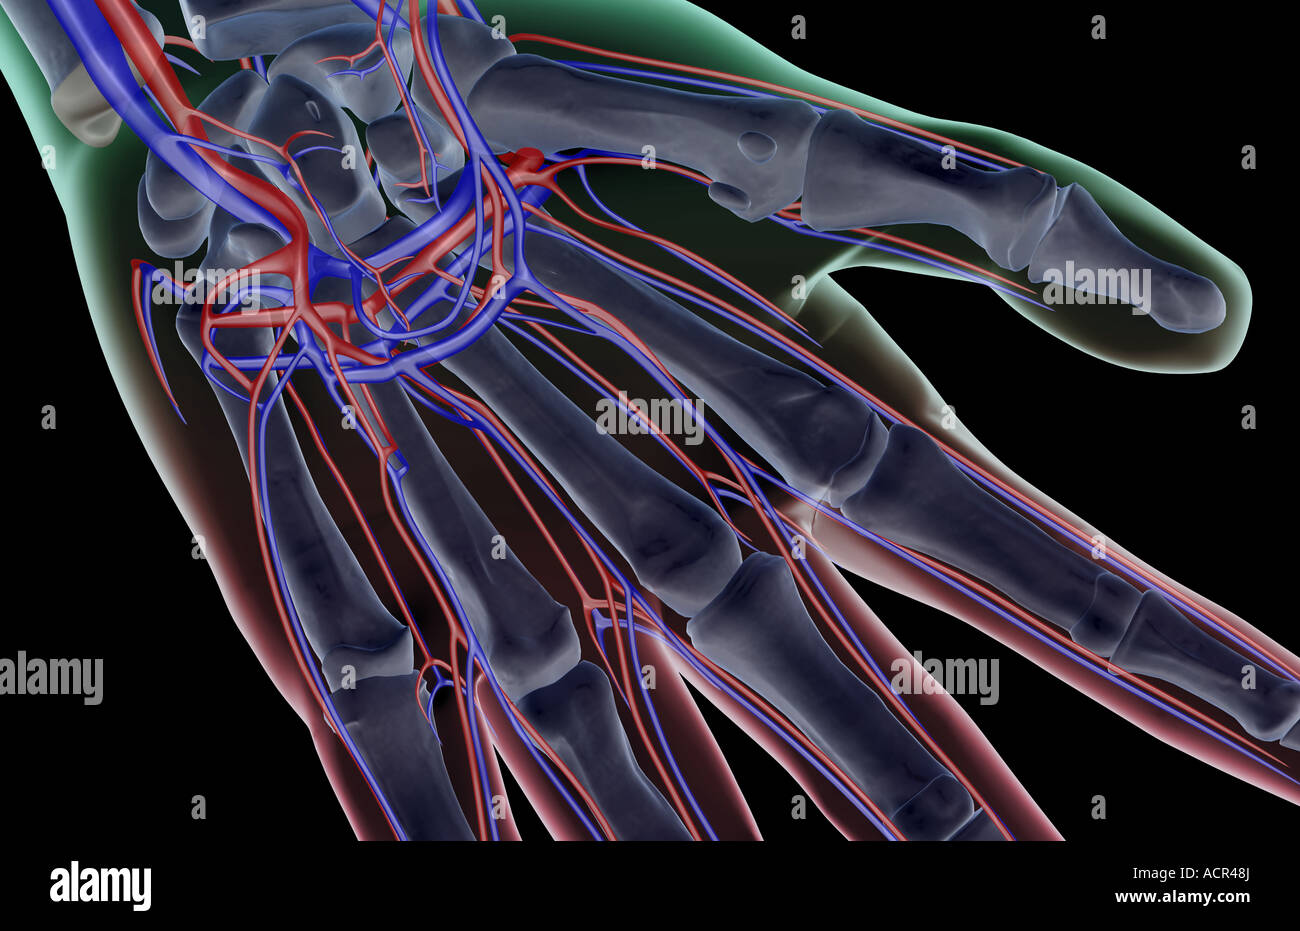

The blood supply of the hand Stock Photohttps://www.alamy.com/image-license-details/?v=1https://www.alamy.com/stock-photo-the-blood-supply-of-the-hand-13213409.html

The blood supply of the hand Stock Photohttps://www.alamy.com/image-license-details/?v=1https://www.alamy.com/stock-photo-the-blood-supply-of-the-hand-13213409.htmlRFACR48J–The blood supply of the hand